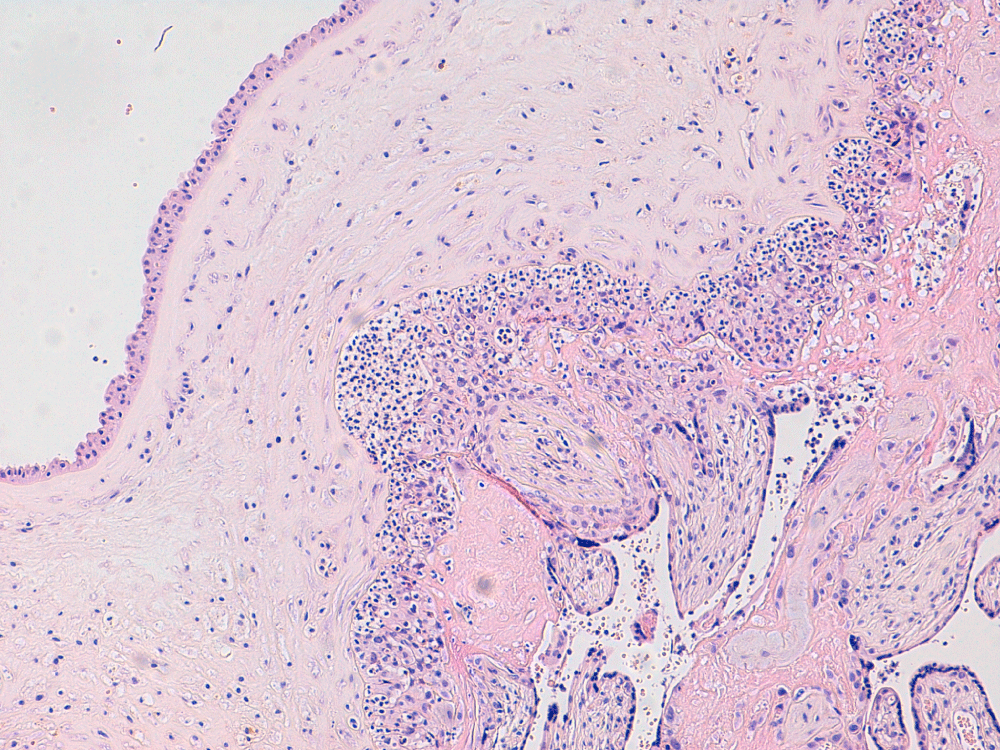

A 26-year-old Caucasian women (gravida 4, para 2) was referred in first trimester to the obstetric department because of an abnormal psychosocial situation. At 22 weeks and 5 days of gestation, she presented with heavy vaginal blood loss. Hemoglobin level was 5.1 mmol/L (8.2 g/dL), showing moderate to severe anemia. Since the placenta was closely inserted to the internal cervical ostium, a marginal placenta insertion was initially thought to be the cause of the bleeding. Haemoglobin levels of 5.7 mmol/L were reached after two packed cells to prevent clinical complications. After two days in hospital, she developed fever (39.0 ℃) with chills. Blood investigations showed elevated infectious parameters, C-reactive protein of 165 mg/L and leukocytes of 24.0/nL. Vaginal ultrasound showed anhydramnios as a result of immature pre-labour rupture of membranes. There was no sign of the previously mentioned low insertion of the placenta, which had probably been an artefact on ultrasound caused by a hematoma. Amoxicillin/clavulanic acid was started intravenously after blood and urine cultures were taken. Maternal sepsis was diagnosed with intrauterine infection and anhydramnios by spontaneous rupture of membranes resulting in an extremely poor prognosis for the fetus. In order to treat and save the patient, the patient gave her consent for induction of labour after the medical condition was explained to her. After administration of mifepristone and misoprostol, she delivered of a lifeless immature girl of 425 grams and the placenta followed easily. The condition of the mother remained stable over time. Serologic assessment showed no recent infection by Toxoplasma, Rubella, Cytomegalic virus or Parvovirus. Herpes simplex IgG and IgM were both negative. Epstein Barr Virus was not tested. Histopathological examination of the placenta showed severe chorioamnionitis with funisitis in two umbilical vessels (Figure 1 and Figure 2). Blood cultures and placenta cultures were positive for Fusobacterium necrophorum. After consultation with the medical microbiologist, the final diagnosis was septicemia, most likely from severe periodontitis. Assessment of the oral cavity by an oral surgeon and a dentist confirmed severe periodontitis (Figure 3). Measurements of pocket depth were not executed because of the presentation of very severe generalised periodontitis. Patient had not been for dental check-up for many years.

Figure 1: Chorioamnionitis with massive influx of neutrophils in the chorionic plate. View Figure 1